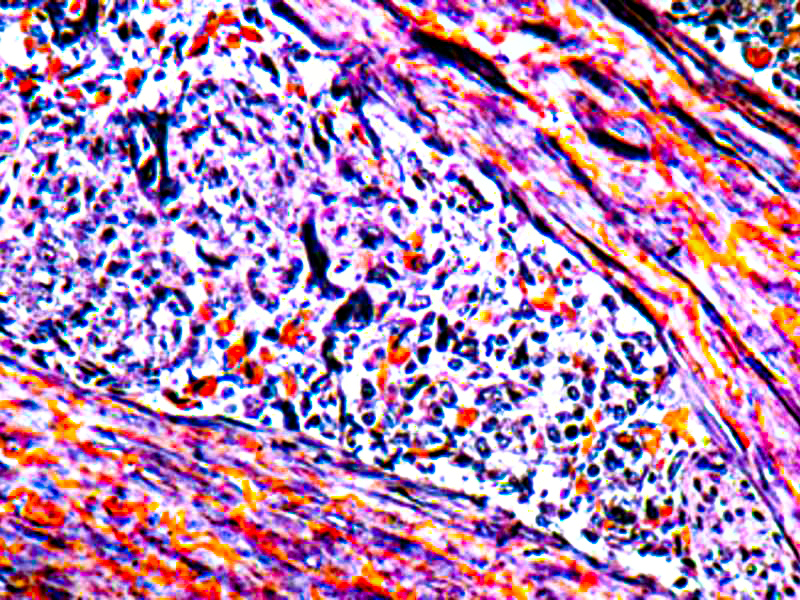

The PTAH Stain Kit is intended for use in the histological visualization of collagen, striated muscle, glial fibers and collagen without using Zenker’s Fixative containing Mercuric Chloride. This kit may be used on formalin-fixed, paraffin-embedded or frozen sections.